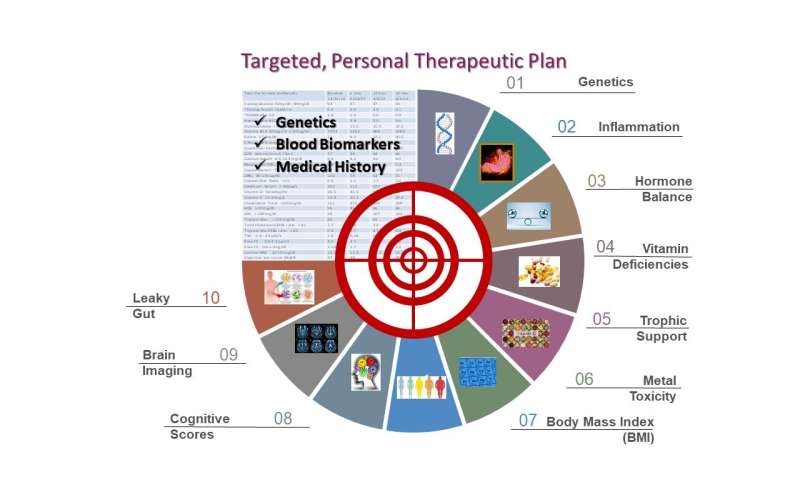

In questo studio su pazienti con vari livelli di declino cognitivo, viene dimostrato come un approccio di precisione e personalizzato porti a stabilizzazione o miglioramento della memoria.

Immagine: Affirmativ Health ha cercato di determinare se un programma completo e personalizzato, progettato per mitigare i fattori di rischio della malattia di Alzheimer, potesse migliorare la funzione cognitiva e metabolica negli individui con declino cognitivo. I risultati hanno dimostrato che questo approccio può migliorare i punteggi dei fattori di rischio e stabilizzare la funzione cognitiva. Credito: Affirmativ Health.

Il team scientifico di Affirmativ Health, dopo un’attenta revisione della ricerca pubblicata, ha sviluppato un approccio globale per affrontare i fattori di rischio supportati scientificamente che sono stati rigorosamente definiti come interventi per promuovere la prevenzione, una maggiore resilienza e la stabilizzazione della funzione cerebrale nel regno dell’ AD e demenza.

“Utilizzando una tecnologia all’avanguardia in concerto con coaching e consulenze, stiamo dimostrando che un approccio multimodale e personalizzato promuove una maggiore resilienza e il ripristino di una funzione cerebrale ottimale. Il programma terapeutico personalizzato comprende genetica, un ampio pannello ematico, anamnesi e dati sullo stile di vita per valutare i fattori di rischio metabolico e i livelli di nutrienti associati alla salute cognitiva.

I livelli di laboratorio target differiscono dalle gamme standard di laboratorio poiché l’obiettivo è raggiungere livelli ottimizzati per la salute cognitiva”, ha affermato Ginger Schechter, MD, Chief Medical Officer, Affirmativ Health.

L’approccio considera oltre 35 fattori noti per contribuire al declino cognitivo. I risultati dimostrano che alcuni di questi fattori sono più colpiti di altri, dimostrando nuovamente la necessità di un piano di trattamento più preciso. “Questo studio supporta la necessità di un approccio incentrato su una misura unica, un approccio che valuta in modo completo tutti i fattori di rischio coinvolti che incidono sulla perdita di memoria“, ha commentato Denise M Kalos, CEO della Affirmativ Health.